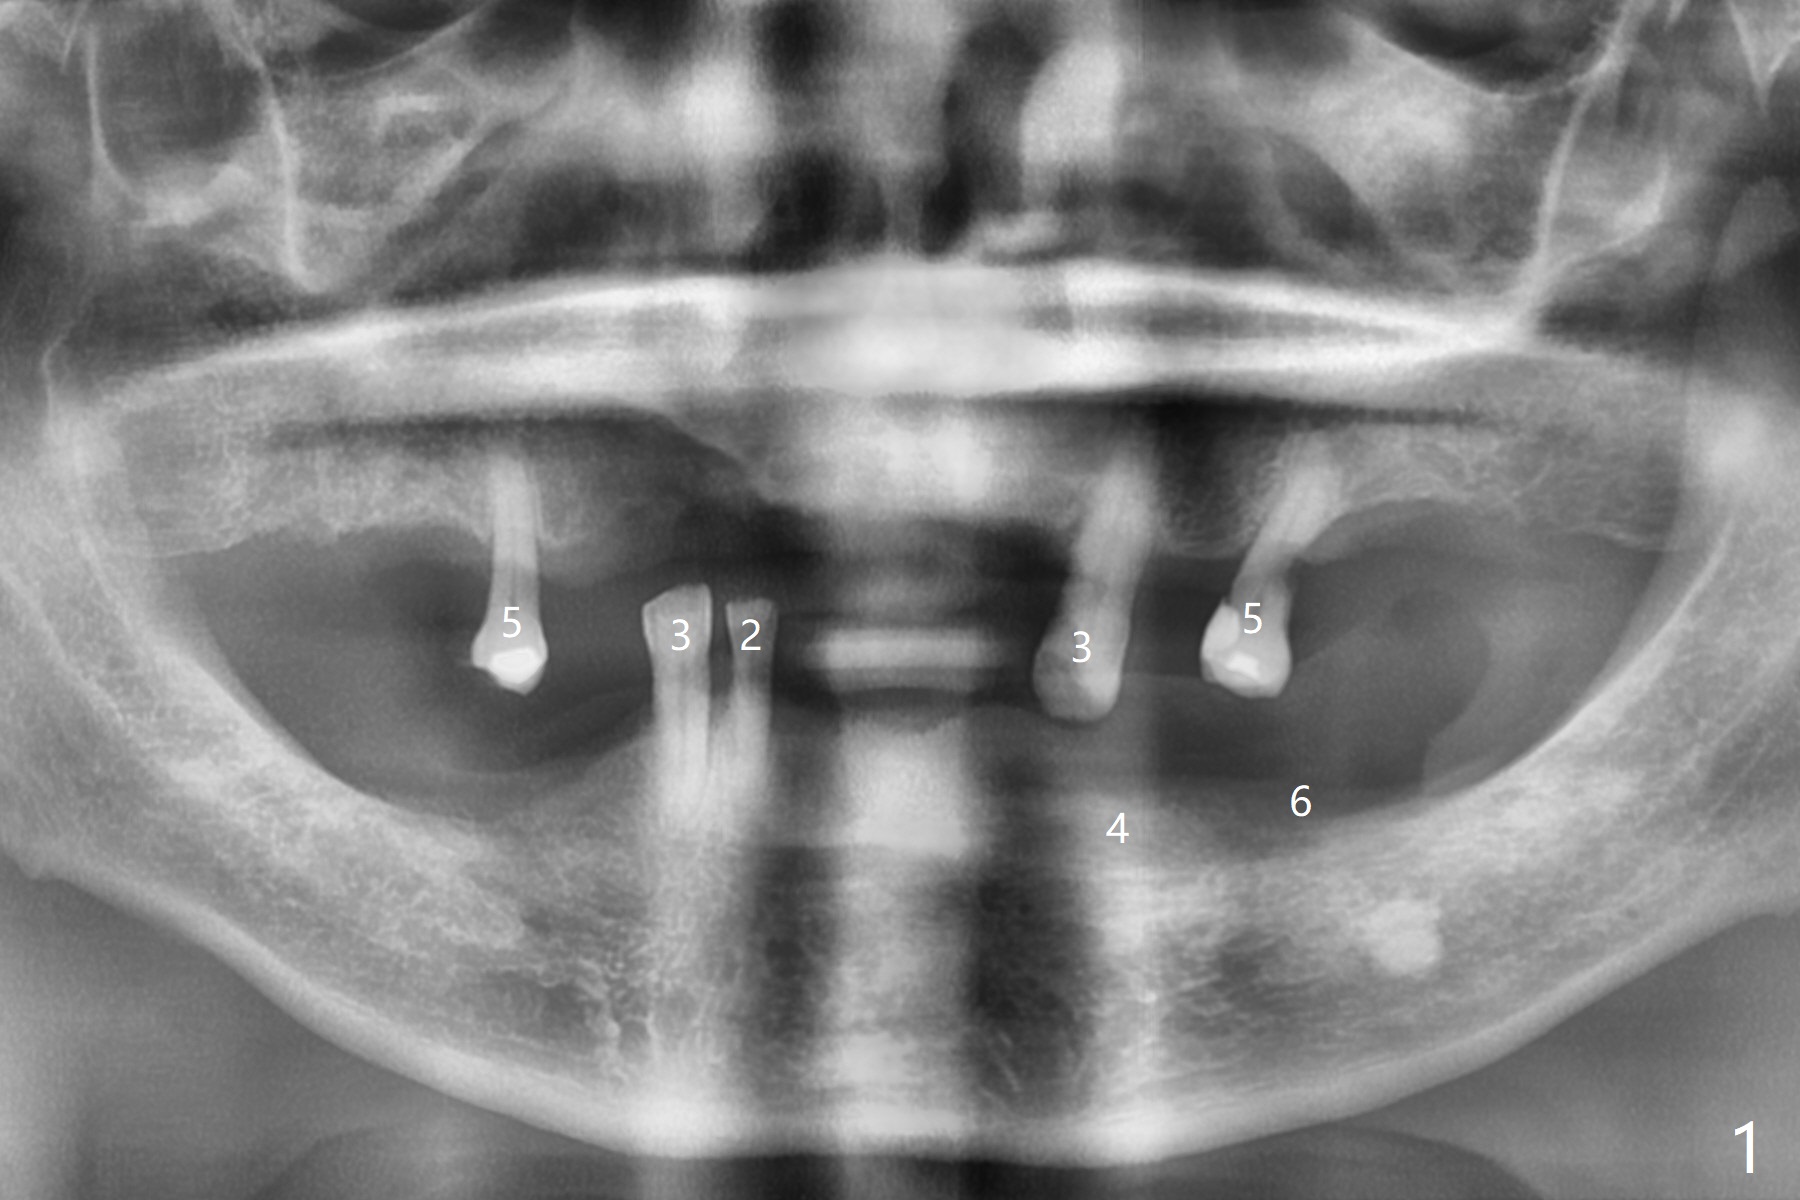

71岁男主诉下颌局部托牙松动(图一),侧切牙不适,临床检查显示后者有咬合创伤,局部卫生不佳,对策:洗牙以及左下4,6植入植体,放置带有球的基台(图五,六)。上颌局部托牙有三个自然牙,挺稳定,但是颈部缺损严重,需要修补(图二,三),左上5远中龋齿需要根管治疗(图四),尽量延长基牙寿命。一个月后病人回来却要求处理松动疼痛右下2,不愿意种植,与3固定和调整咬合,症状消失。Return to No Caries Overdentures Xin Wei, DDS, PhD, MS 1st edition 11/18/2020, last revision 12/13/2020